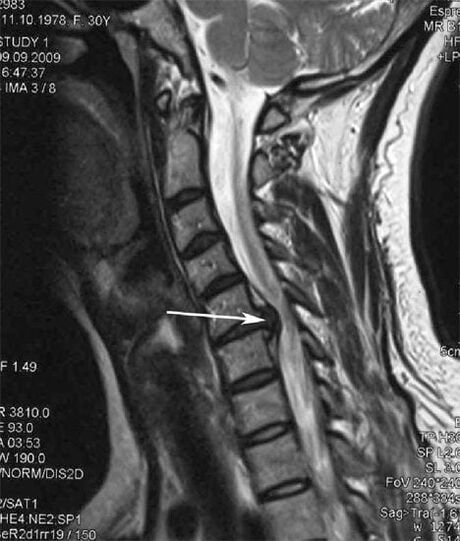

| Zervikal Osteochondrose | D’Erscheinung vu pathologesche Verännerungen an engem oder méi Spinalbewegungssegmenter. Behënnerte Spinal Mobilitéit, Entwécklung vu myofasciale Schmerzsyndromen a Prise vu Spinalwurzelen | Péng, Parästhesie a Motorstéierungen an der Gebärmutterhalsregioun, déi sech op d’Réck vum Kapp an den ieweschte Glieder verbreet. Detektioun vu charakteristesche Verännerungen an der Wirbelsäule op MRI a Röntgenbilder (Osteophyten, ofgeholl Distanz tëscht Wirbelen, Zeeche vu Schied un intervertebrale Gelenker) |

An den initialen Etappen gëtt Osteochondrose mat MRI festgestallt. Spéider kann Pathologie diagnostizéiert ginn duerch Radiographie. Op Röntgenbilder vun der Gebärmutterhalskierch gëtt eng Ofsenkung vun der Distanz tëscht de Wirbelen, pathologesch Verännerungen an de Facettegelenken an Osteophytose bemierkbar.

Vill Leit beschwéieren datt se hiren Hals net kënnen ëmdréinen wéinst schwéiere Péng, deen optrieden nodeems se op eemol eppes Schwéier ophiewen. Dëst Phänomen weist op d'Bildung vun enger herniéierter Disc. D'Ursaach vu Schmerz am Réck, am Hals an der ieweschter Gliedmaart ass eng Prise vun enger vun den Nerve Wuerzelen aus der Wirbelsäule.